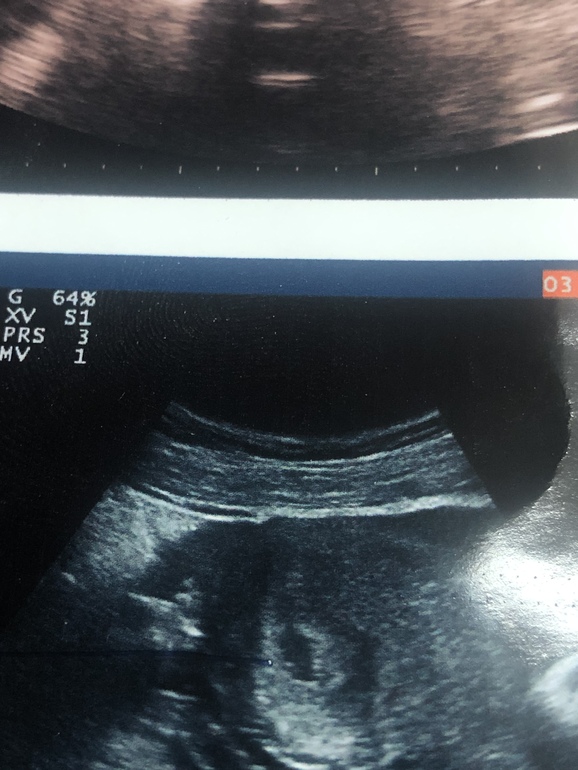

Вчера сходила на первое УЗИ, 20ДПП( акушерские 5,3 недели), увидели деформированное ПЯ 7мм и гипертонус по передней стенке. Делала узи не там где ЭКО, пошла в другую т.к уехала на праздники из города. У меня ещё ГСЯ средней формы( яичник один 9см, второй 7см и куча естественно кист) я ей не стала говорить что ЭКО, так она чуть в обморок не упала и жидкость говорит 180мг в позаматочном пространстве. Я чувствую себя отлично, ничего не беспокоит. ХГЧ последнее делала на 13дпп был 1200. Вообщем сказала она мне что плодное яйцо маленькое и пустое. Всю ночь не спала только ревела.

У меня на 19 дпп было плодное яйцо 6 мм , без эмбриона и жм.

Все хорошо в итоге, чего и вам желаю!

У меня такие же страхи, с первой дочкой вообще не заморачивалась, а щас на 20 дпп пя всего 4,5мм🥺 Узи врач и Ре говорят все норм, жм визуализируется. Эмбриона конечно не видно, послезавтра контрольное узи, надеюсь наш малыш вырос 🙏🏻🙏🏻🙏🏻 тоже всякого начиталась😰